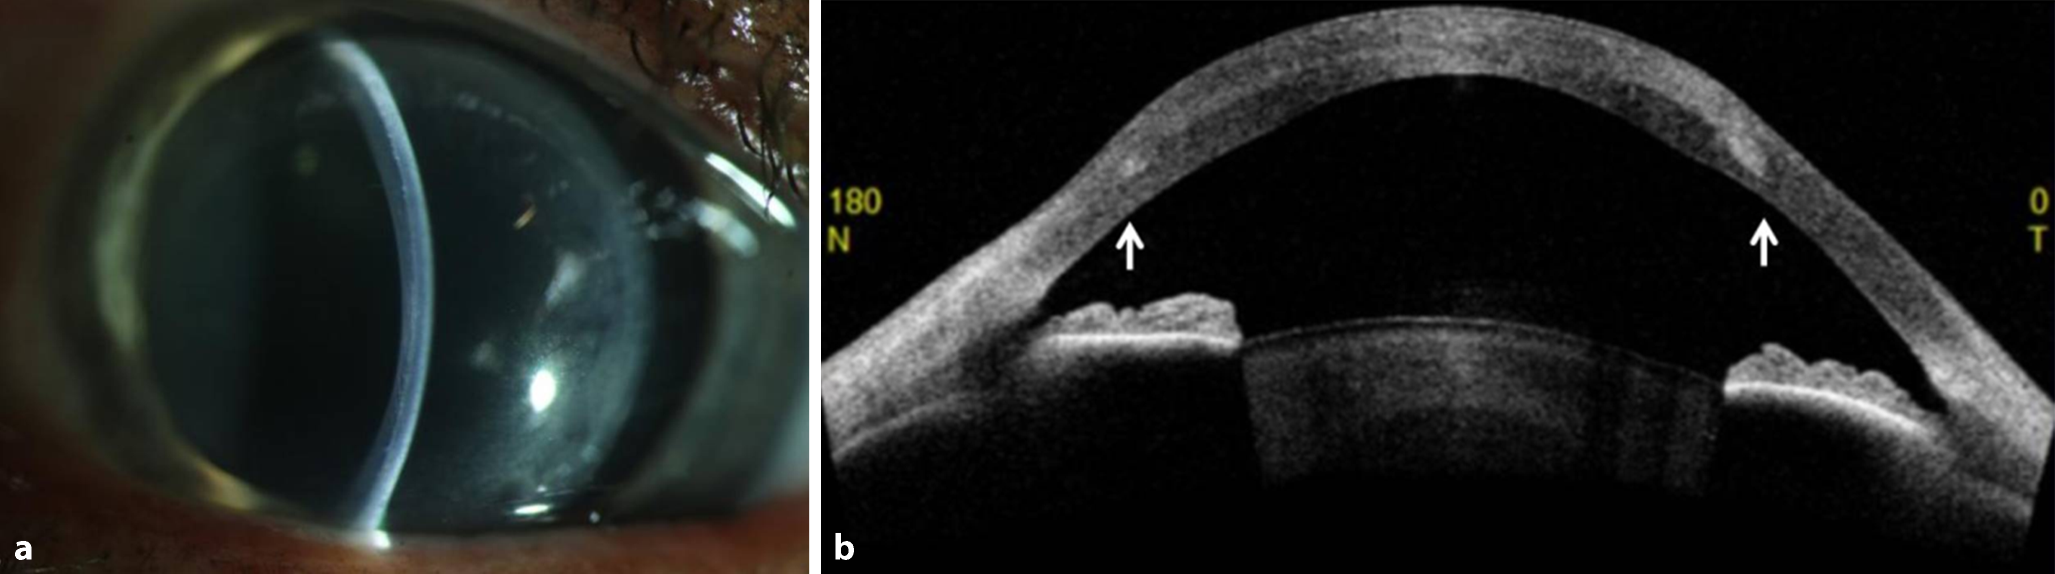

Bei einer inzwischen 60 Jahre alten Patientin war im Jahr 1982 die Erstdiagnose eines Keratokonus gestellt worden. Aufgrund einer Kontaktlinsenunverträglichkeit und eines letztlich unzureichenden Visus mit Brille am linken Auge wurde sie im Jahr 2008 extern laut eigener Anamnese und Überweisung mittels „Keratoplastik“ behandelt. Spaltlampenmikroskopisch zeigte sich eine gut kompensierte, aber global verdickte Hornhaut mit in etwa 50 % Stromatiefe durchgängig verlaufender Grenzlinie (Abb. 1a). In der optischen Kohärenztomographie (OCT) des Vorderabschnitts zeigte sich die Wirtshornhaut intakt ohne Trepanationsgrenzfläche, aber mit einem auf der Wirtshornhaut fixierten Stromalentikel (Abb. 1b). Die Spiegelmikroskopie zeigte ein intaktes Wirtshornhautendothel mit einer Messung von 2753 Zellen pro Quadratmillimeter. Die Scheimpflug-Bildgebung zeigte einen schrägen regulären Astigmatismus, die Kmax betrug 58,4 dpt und die dünnste Pachymetrie 781 µm. Die Patientin erreichte einen brillenkorrigierten Fernvisus von 0,6 (−3,00/−4,50/31°).

Abb. 1

a Spaltphoto, Grenzlinie in etwa 50% Stromatiefe, b intakte Wirtshornhaut (Pfeile) mit darüber fixiertem Stromalentikel